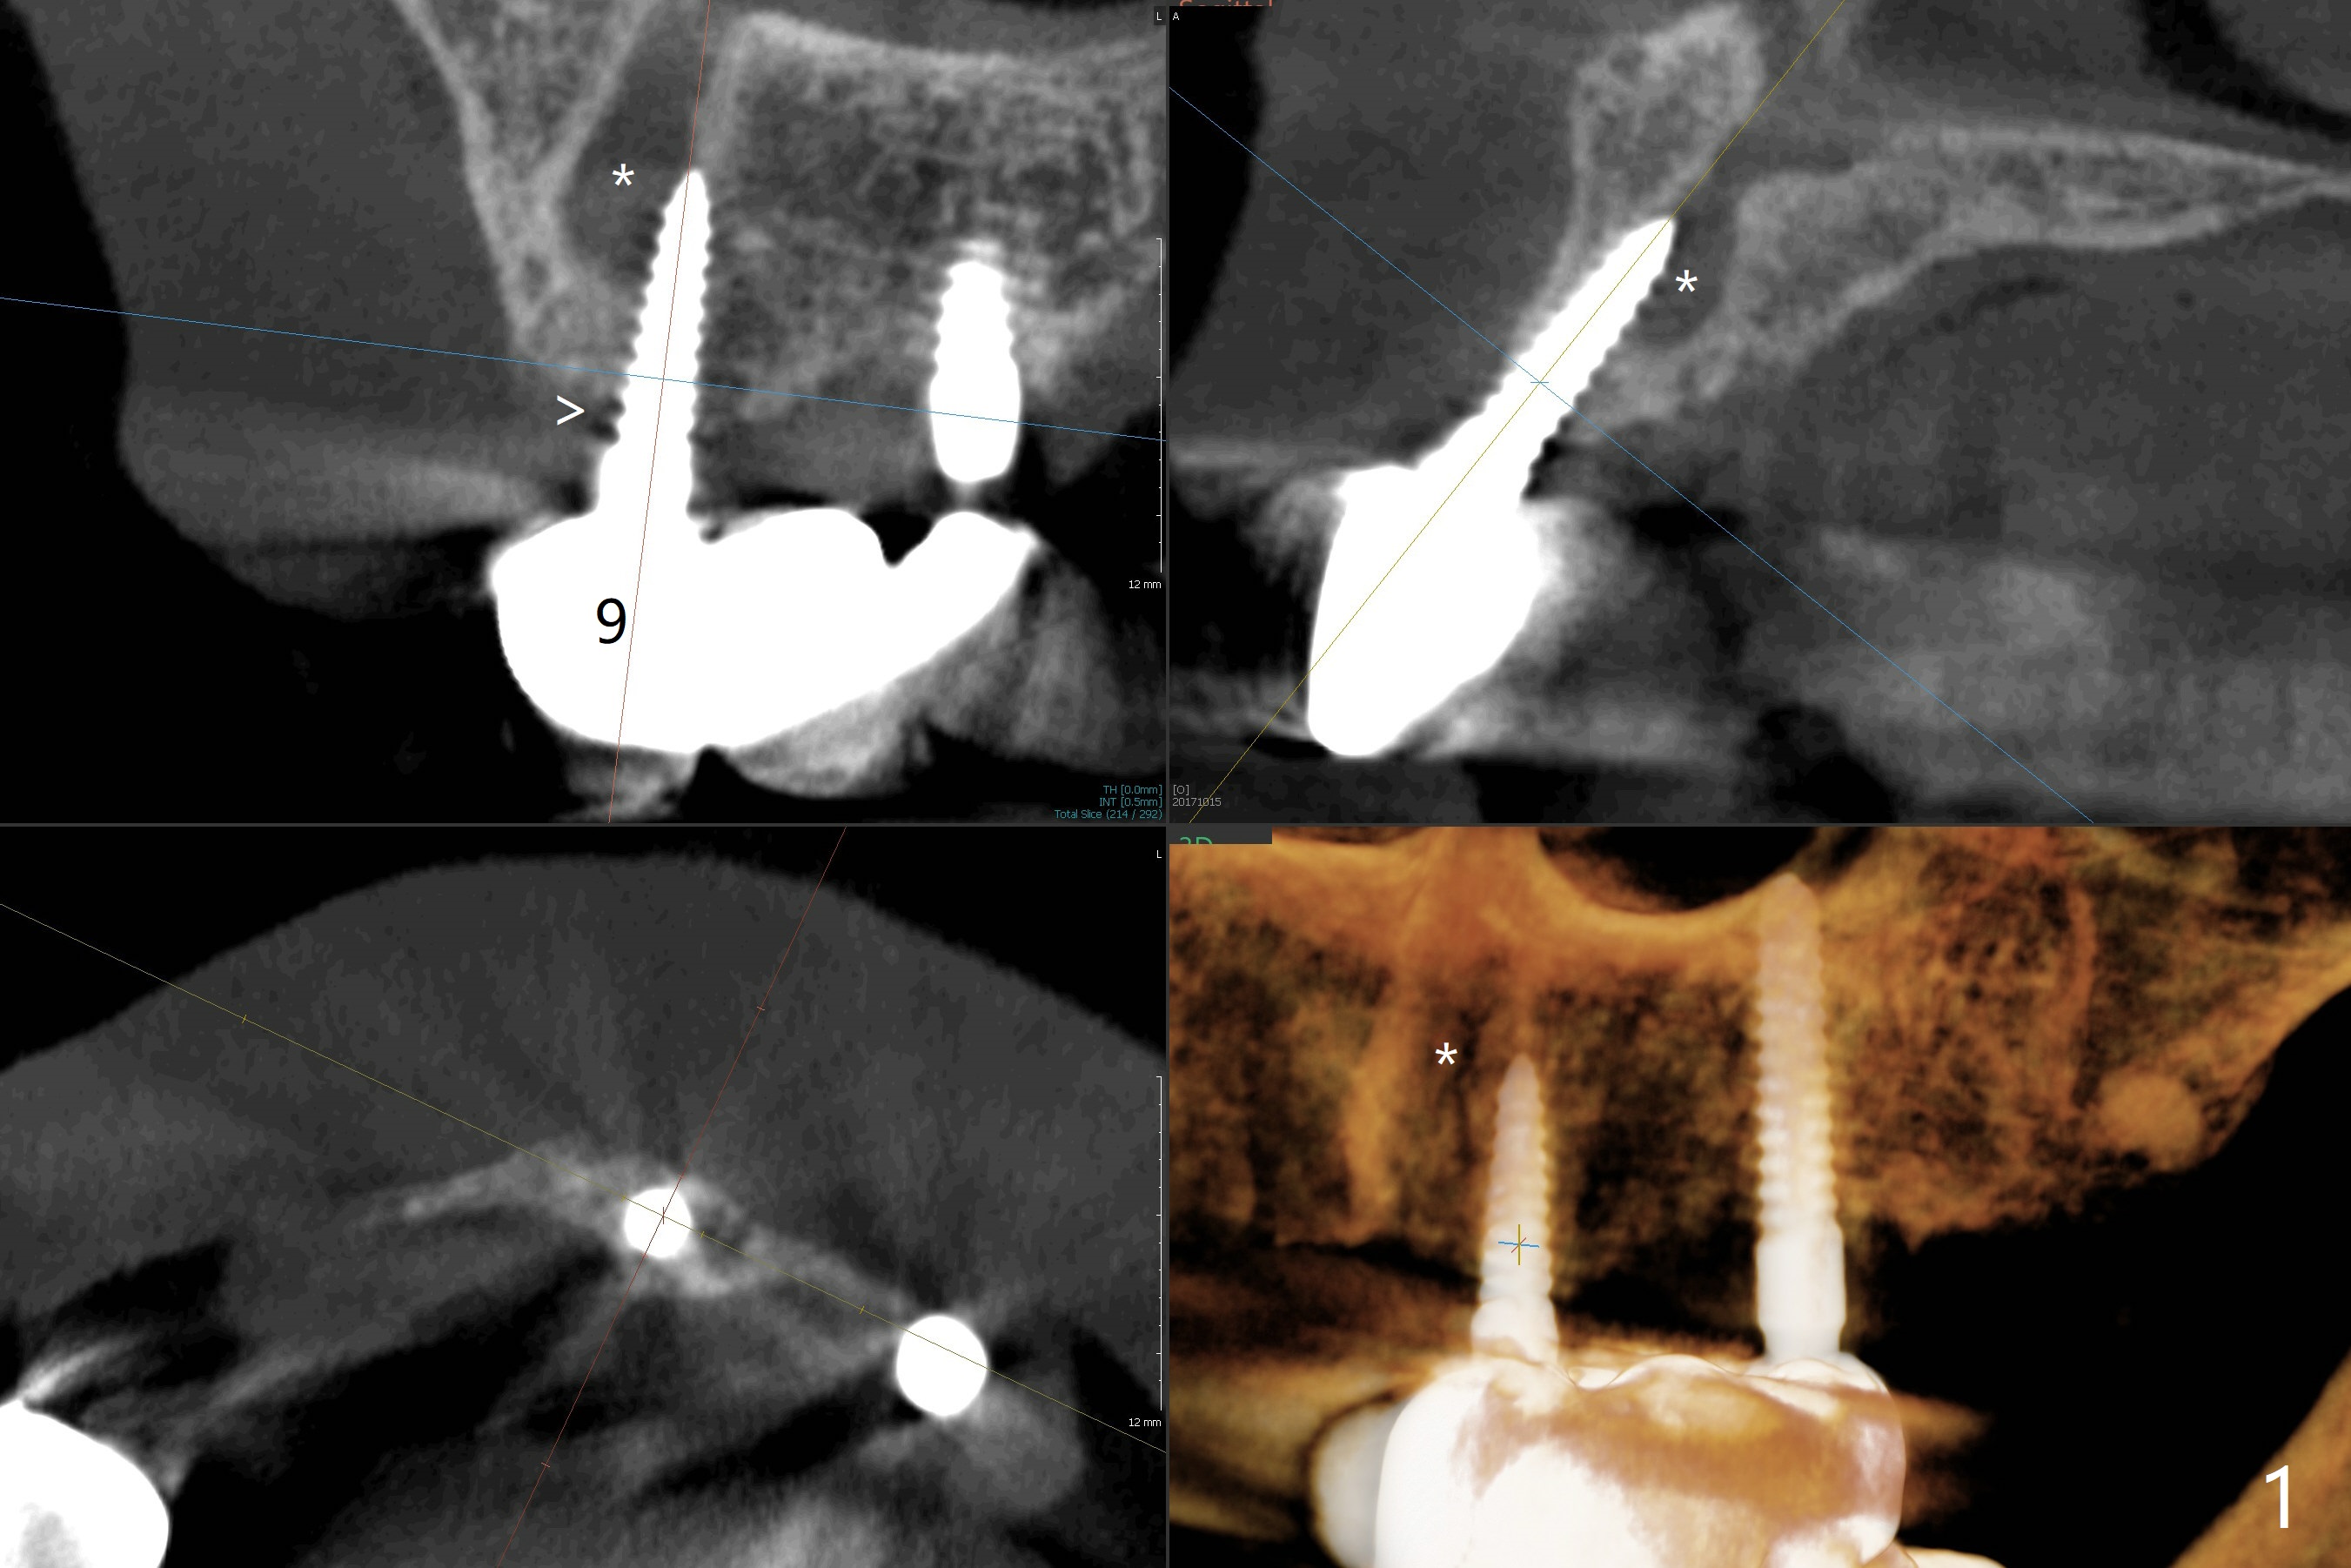

A 65-year-old woman will return to clinic with chief complaint of "loose top left implant bridge" 2.5 years post cementation. It appears that the implant at #9 is placed into the incisive canal (Fig.1 *) with coronal implant thread exposure (>). If it is true that the problem is #9. The denture tooth #8 will be removed so that the upper partial denture will be used a guide. One-piece implants will be placed at #8 and 10. The implant at #9 will be removed for bone graft as a future implant site, since the implant at #10 is 2 mm in diameter, vulnerable to fracture under mastication. If her vein is thin for PRF, consider using GEM21S to hydrate cortical bone. In fact the implant at #9 fractures at the junction of bone loss (Fig.4,5 ^). Full-mouth CT will be taken. Alginate impression will be taken for #8-10 surgical stent and provisional. Remove #8 denture tooth for implant placement with incision. Section the FPD between #10 and 11 for #10 implant placement using #9 broken implant as a guide when PA is taken. Remove the fractured implant and make a provisional.